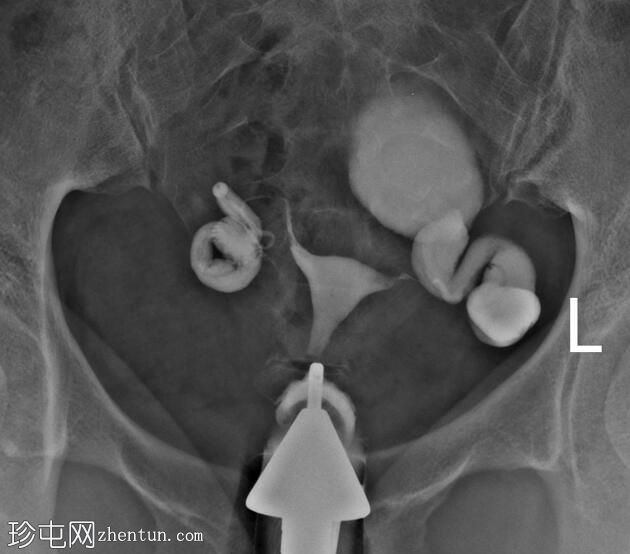

子宫体位于盆腔中线,形态及轮廓正常。

宫颈管长度正常,黏膜表面扩张良好。

右侧输卵管扩张并充满液体,无腹膜溢出,提示输卵管积水及输卵管阻塞。

左侧输卵管亦扩张并充满液体,伴有造影剂残留及少量溢出,提示输卵管积水及输卵管阻塞。

此外,左侧盆腔内,位于输卵管上内侧,可见大量分隔的造影剂积聚,并伴有盆腔输卵管周围粘连。

子宫输卵管造影结果符合双侧输卵管阻塞和输卵管积水,左侧输卵管周围可见分隔的造影剂渗漏。